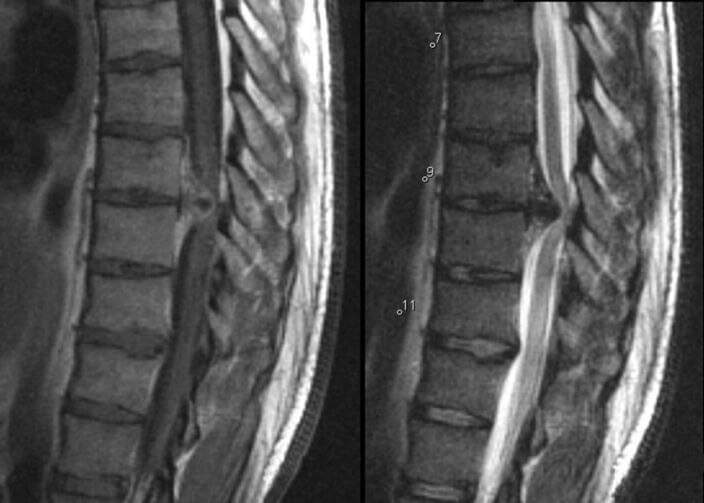

Physiotherapy clinic in tambaram Are you Looking for Physiotherapy Treatment, sunshine super speciality physiotherapy clinic, #physiotherapyclinicintambaram, Exercise and Manual Therapy, orthopedic and Neuro Rehabilitation, Post Operative Physiotherapy Treatment, Fracture Rehabilitation, pain free movement. Pain clinic in Tambaram Pain is the most common symptom of a thoracic herniated disc and may be isolated to the upper back or radiate in a dermatomal (single nerve root) pattern. Thoracic back pain may be exacerbated when coughing or sneezing. Radiating pain may be perceived to be in the chest or belly, and this leads to a quite different diagnosis that will need to include an assessment of heart, lung, kidney and gastrointestinal disorders as well as other non-spine musculoskeletal causes. Within the spine itself there are also many other disorders that can have similar presenting symptoms of upper back pain and/or radiating pain, such as a spine fracture (e.g. from osteoporosis), infection, tumor, and certain metabolic disorders.. For more info visit us at http://www.topspinesurgeon.in/latest-update/pain-is-the-most-com/188?utm_source=facebookpage SUNSHINE ® SUPER SPECIALITY PHYSIOTHERAPY CLINIC - #Drparthiban #Sunshinephsiotherapyclinic #Physiotherapy clinicintambaram #Physiotherapyclinic DR.M.P. PARTHIBAN.M.P.T (Ortho), Chief Orthopedic Physiotherapist, Call for Appointments: - 9345122177 East Tambaram, CHENNAI